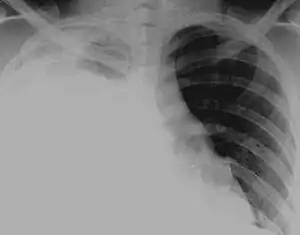

Hydrothorax is a type of pleural effusion in which transudate accumulates in the pleural cavity. This condition is most likely to develop secondary to congestive heart failure, following an increase in hydrostatic pressure within the lungs. More rarely, hydrothorax can develop in 10% of patients with ascites which is called hepatic hydrothorax. It is often difficult to manage in end-stage liver failure and often fails to respond to therapy.